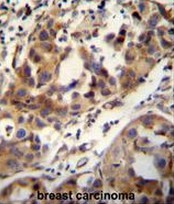

- Main image

- Experimental details

- CCDC17 antibody (C-term) (Cat. #AP50772PU-N) immunohistochemistry analysis in formalin fixed and paraffin embedded human breast carcinoma followed by peroxidase conjugation of the secondary antibody and DAB staining.This data demonstrates the use of the CCDC17 antibody (C-term) for immunohistochemistry. Clinical relevance has not been evaluated.